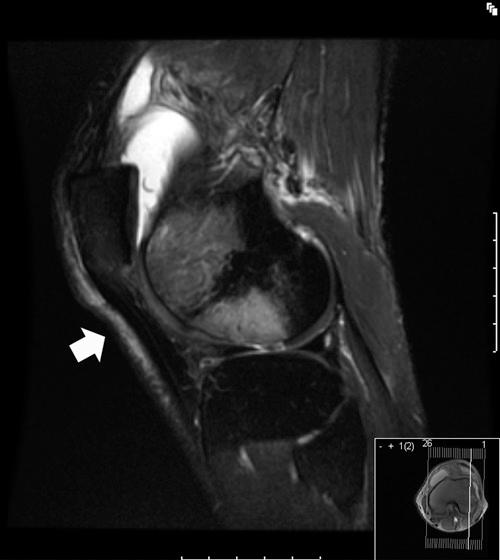

Although disorders of the patellofemoral joint are common in the athlete, their management can be challenging and require a thorough physical examination and radiologic evaluation, including advanced magnetic resonance imaging techniques.

Physical examination and imaging evaluation including standard radiographs are crucial in identifying evidence of malalignment or instability. Magnetic resonance imaging provides valuable information about concomitant soft tissue injuries to the medial stabilizers as well as injuries to the articular cartilage, including chondral shears and osteochondral fractures. Quantitative magnetic resonance imaging assessing the ultrastructure of cartilage has shown high correlation with histology and may be useful for timing surgery.

Evaluation of patellofemoral disorders is complex and requires a comprehensive assessment. Recent advancements in imaging have made possible a more precise evaluation of the individual anatomy of the patient, addressing issues of malalignment, instability, and underlying cartilage damage.